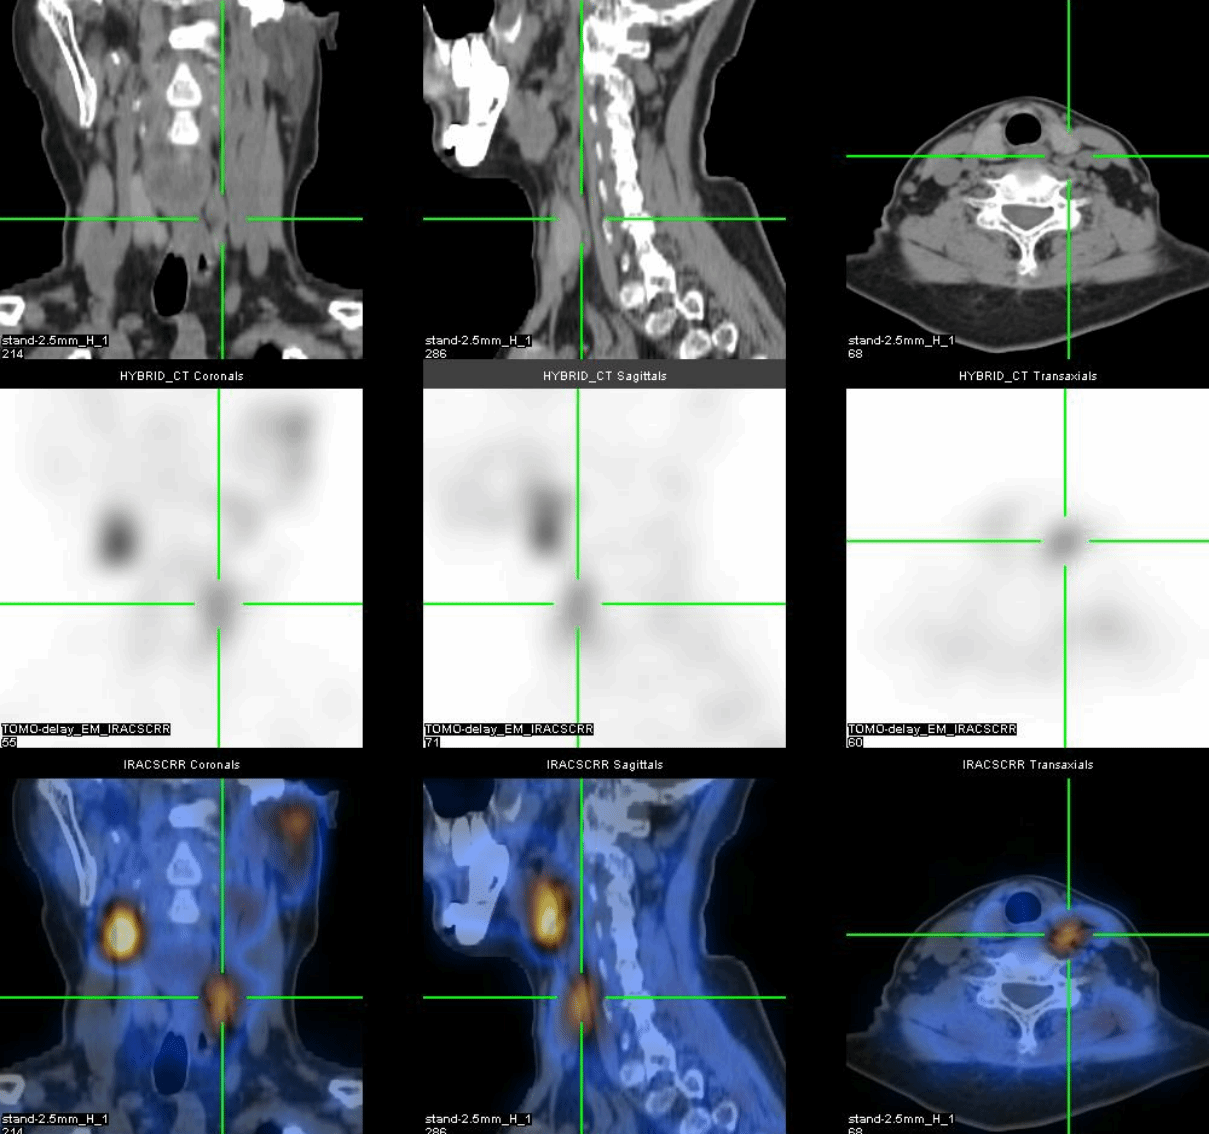

进一步的SPECT/CT断层融合显像(图2-4)显示:肋骨、肩胛骨、骶骨等灶性异常显像剂浓聚处伴骨质膨胀性骨质破坏。

通过全身显像,可以判断这些异常并非骨转移瘤所引起,而是一种代谢性骨病,结合SPECT/CT所示多发溶骨性骨质膨胀性破坏,考虑为甲状旁腺功能亢进所致代谢性骨病伴棕色瘤。为了进一步验证,段阿姨进行了血清电解质和甲状旁腺激素的测定,结果显示她的血清钙(3.14mmol/L)和甲状旁腺激素(1548pg/ml)水平明显增高,从而证实了甲状旁腺功能亢进症的诊断。段阿姨无慢性肾脏疾病、骨软化症、肠吸收不良综合征、维生素D缺乏等疾病的病史,因此诊断为原发性甲状旁腺功能亢进症。原发性甲状旁腺功能亢进症首选治疗方法为手术[1],而手术的成功主要取决于术前对功能亢进的甲状旁腺病变的精确定位,甲状旁腺显像则对识别功能亢进的甲状旁腺病变具有非常重要的意义[2]。